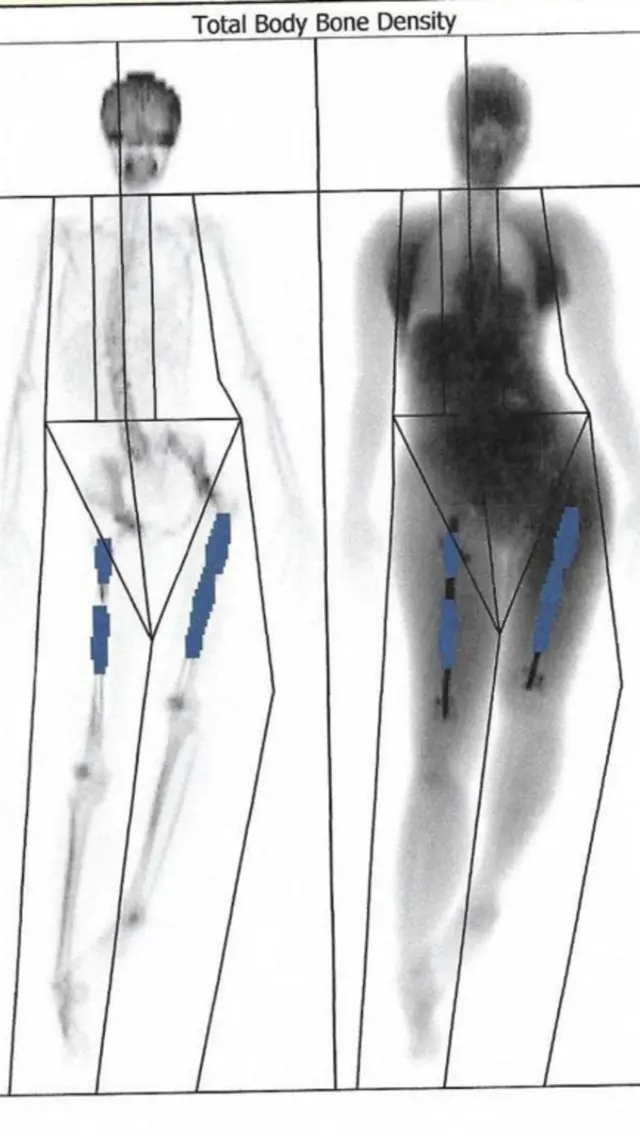

ఈ ప్రొసీజర్లో కొంత నొప్పి ఉంటుందని ఊహించాం. కానీ, ఆపరేషన్ సమయంలో కాళ్ల ఎముకలు రెండుగా చీల్చారు. లోహపు కడ్డీలు లోపల పెట్టారు.

ఈ లోహపు కడ్డీలు వాటి పొడవును పెంచుకునేందుకు క్రమంగా విస్తరిస్తాయి. ఈ సమయంలో ఎముక రెండు భాగాలు వేరువేరుగా అవుతాయి. ఈ ప్రక్రియ మెల్లగా రోగి ఎత్తును పెంచేందుకు ఉపయోగపడుతుంది. విరిగిన ఎముకలు తిరిగి క్రమంగా అతుక్కోవాలి. వాటి మధ్యలో ఉన్న గ్యాప్ను పూడ్చుకోవాలి. ఈ ఆపరేషన్ చాలా క్లిష్టమైంది.

మరో అదనపు ఆపరేషన్ కోసం వేల పౌండ్లు ఖర్చవుతుందని చెప్పినట్లు ఎలైన్ తెలిపారు. సెప్టెంబర్ నాటికి కుడి కాలు 7 సెంటిమీటర్ల మేర పెరిగింది. కానీ, అంతా అనుకున్నట్లు జరగలేదు. కుడి, ఎడమ కాళ్ల పొడవులో తేడా వచ్చింది. అది ఆమెకు సమస్యగా మారింది. ఆమె వెన్నుముక వంకర్లు తిరిగింది.

ఆరు వారాల తరువాత, ఆమె కుడి కాలును స్కాన్ చేసినప్పుడు ఎముకల పెరుగుదల తక్కువగా ఉన్నట్లు తెలిసింది.